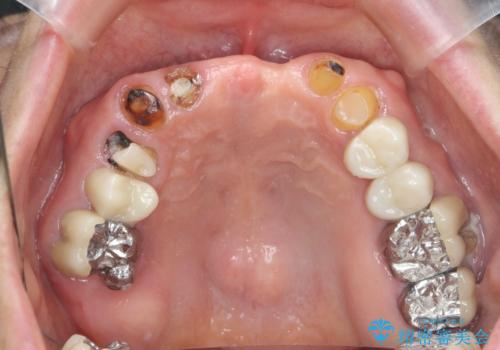

歯が割れているといわれた 奥歯にインプラントをしていきたい 全体的な治療

できる限り口の中を綺麗にしたい。